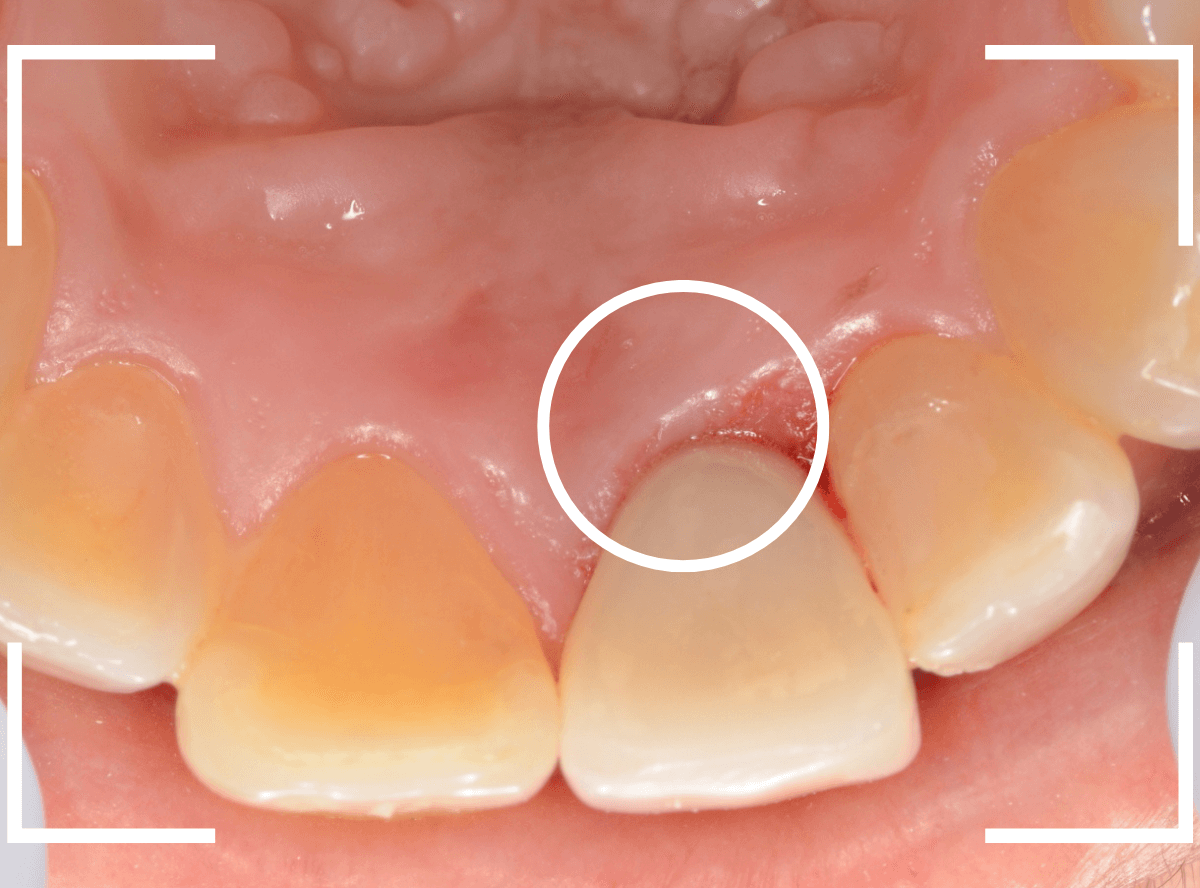

まずは虫歯のある歯の治療とファイバーコアのsetを行い、支えとなる歯(支台歯)の形を整えます。

完成の前に、ジルコニアフレームにワックスを盛ったもので、患者さんと完成型のシュミレーションをします。

患者さんからも、ゴーサインをもらったのを確認して、完成させます。

微調整をして、最終setしたところです。

無事にメタルコアを除去できましたので、ファイバーコアに置き換えます。

歯肉の治療がひと段落したところで、ジルコニア・セラミックで再製しました。